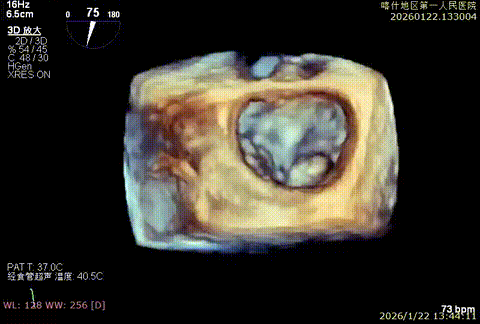

3D enface脱垂情况

X-plan 反流情况

3D enface组织桥稳定

3D enface组织桥

3D enface 组织桥稳定

3D enface 反流少量